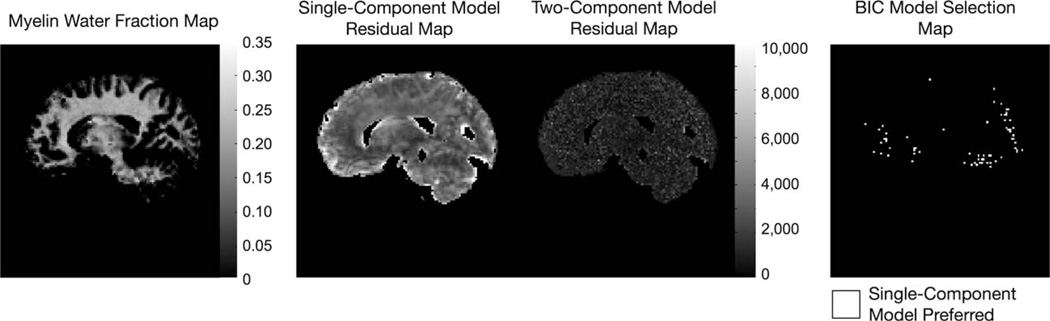

A potential pitfall of complex models is “over-fitting” the data, i.e., extracting information from models not supported by the data. To avoid this, one can use any number of parsimony metrics or statistical tests to justify the use of more complex models. Using the acquired 3 T data, we compared the conventional single-component DESPOT1 and DESPOT2 fits with the more complex two component mcDESPOT fit. Residuals to the single- and two-component fits were calculated and then compared using the Bayesian information criterion (BIC), (18) to determine which model was better supported by the data. The BIC compares the magnitude of the residuals while penalizing for the number of estimated parameters.

Finally, results of the single- and two-component residuals and BIC analysis are shown in Fig. 14. Despite the complexity of the two component mcDESPOT model, this analysis shows the mcDESPOT model is justified by the data throughout the majority of the image.

FIG. 14.

Analysis of residuals and model selection. To illustrate the improved fit, and justify the more complex two-component fit, cumulative residuals to the single-component T1 and T2 fits, as well as two-component mcDESPOT residuals are shown alongside a myelin fraction image derived from 3 T mcDESPOT data. In the BIC model selection map, white voxels correspond to those in which the single-component model is preferred. The BIC parsimony metric shows the two component model is preferred across the majority of voxels.